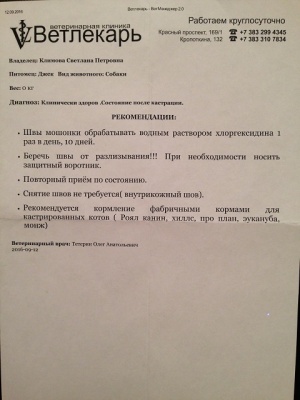

– кастрация по проекту «Все в моих руках», клиника Ветлекарь, хирург Тетерин Олег Анатольевич (чек 2, товарный чек 2, согласие на операцию – документ 2, рекомендации – документ 2-2) – 1500 руб.;

– кастрация по проекту «Все в моих руках», клиника Ветлекарь, хирург Тетерин Олег Анатольевич (чек 2, товарный чек 2, согласие на операцию – документ 2, рекомендации – документ 2-2) – 1500 руб.;

12.09.2016, перед началом пиара, проведена кастрация в клинике Ветлекарь, по льготной программе Все в моих руках. Кастрировал Джека сам Олег Анатольевич Тетерин.

12.09.2016, перед началом пиара, проведена кастрация в клинике Ветлекарь, по льготной программе Все в моих руках. Кастрировал Джека сам Олег Анатольевич Тетерин.